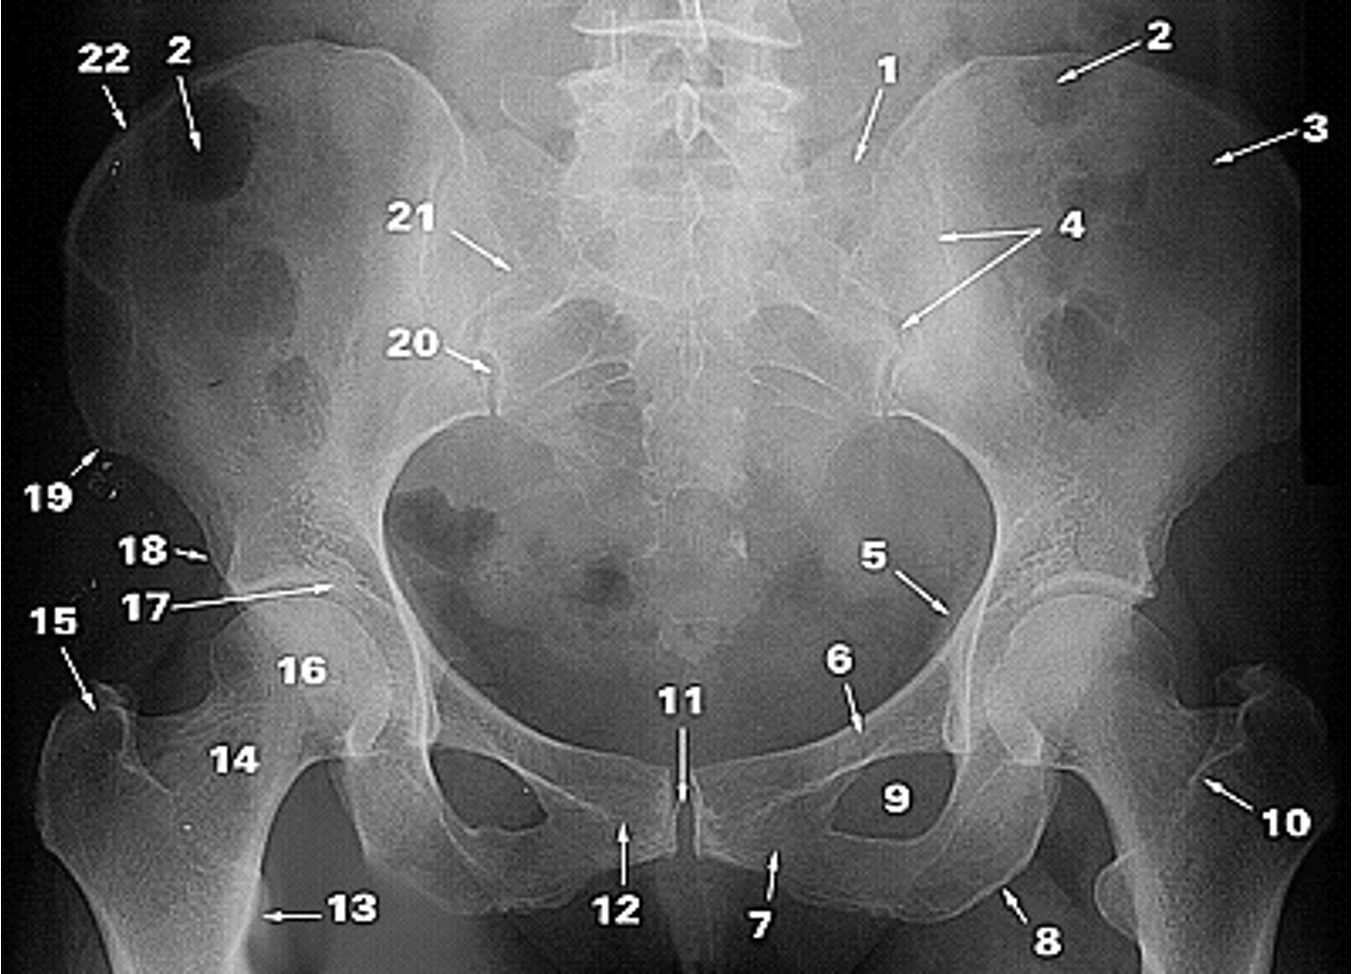

<p>1.</p>

1.

Lateral Part of the Sacrum

2

New cards

<p>2.</p>

2.

Gas in colon

3

<p>3.</p>

3.

Ilium

4

<p>4.</p>

4.

Sacroiliac Joint

5

<p>5.</p>

5.

Ischial Spine

6

<p>6.</p>

6.

Superior Ramus of Pubis

7

<p>7.</p>

7.

Inferior Ramus of Pubis

8

<p>8.</p>

8.

Ischial Tuberosity

9

<p>9.</p>

9.

Obturator Foramen

10

<p>10.</p>

10.

Intertrochanteric Crest

11

<p>11.</p>

11.

Pubic Symphysis

12

<p>12.</p>

12.

Pubic Tubercle

13

<p>13.</p>

13.

Lesser Trochanter

14

<p>14.</p>

14.

Neck of Femur

15

<p>15.</p>

15.

Greater Trochanter

16

<p>16.</p>

16.

Head of Femur

17

<p>17.</p>

17.

Acetabular Fossa

18

<p>18.</p>

18.

Anterior Inferior Iliac Spine

19

<p>19.</p>

19.

Anterior Superior Iliac Spine

20

<p>20.</p>

20.

Posterior Inferior Iliac Spine

21

<p>21.</p>

21.

Posterior Superior Iliac Spine

22

<p>22.</p>

22.

Iliac Crest